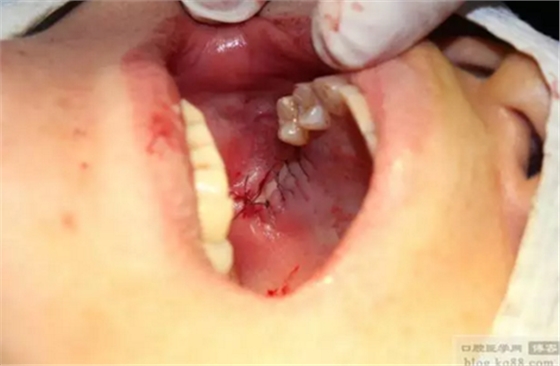

同期植入植體。

縫合。